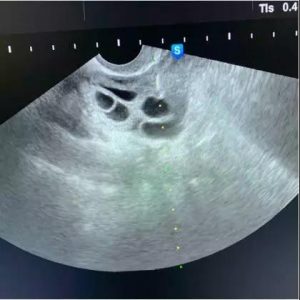

像这种情况,穿刺针进去就是卵泡,还没来得及疼呢手术就结束了!